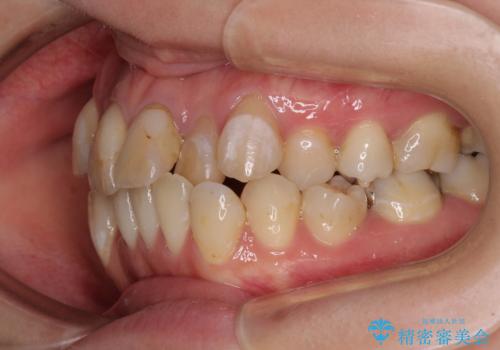

- 前歯の八重歯やデコボコを気にして来院された患者様です。

口元の突出感はありませんが、前歯の重なりが著しいため、目立ちにくい表側のワイヤー装置にて、上下左右の第一小臼歯4本を抜歯して矯正治療を行うこととしました。

上顎前歯4本は、以前むし歯により神経をすべて取り除かれており、その影響で既に変色を起こしている状態でした。